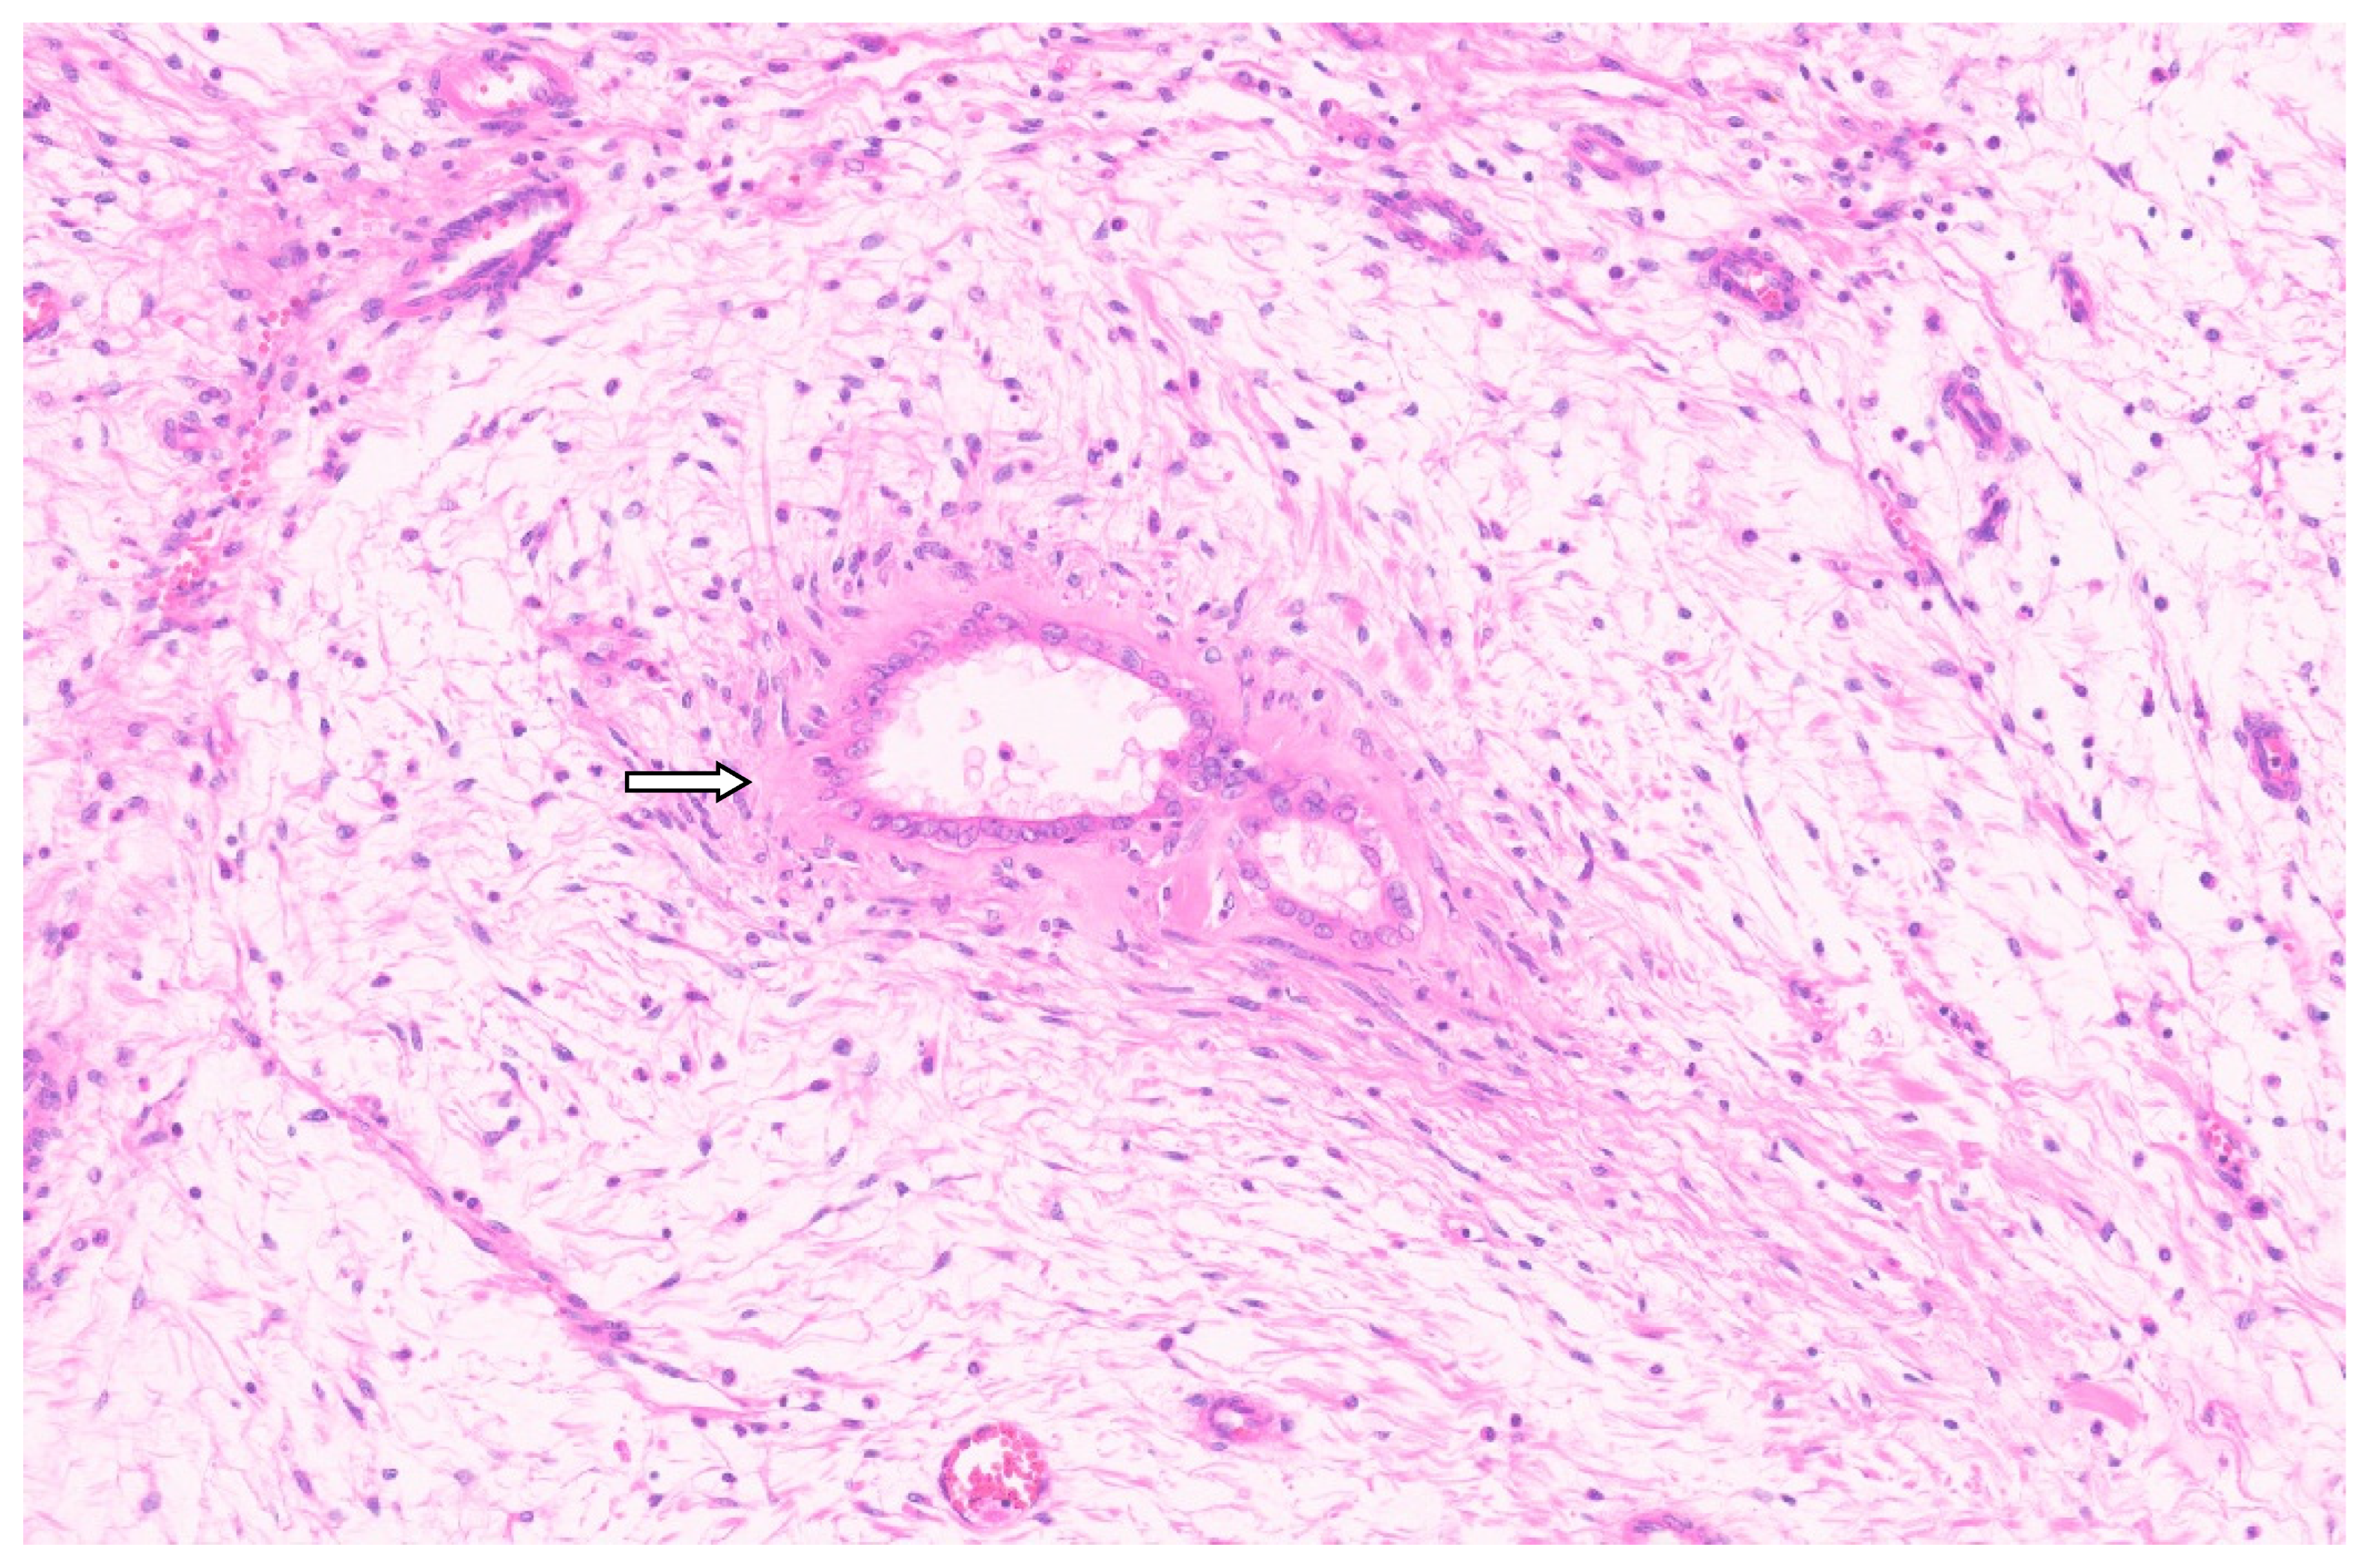

8.4. Pathology